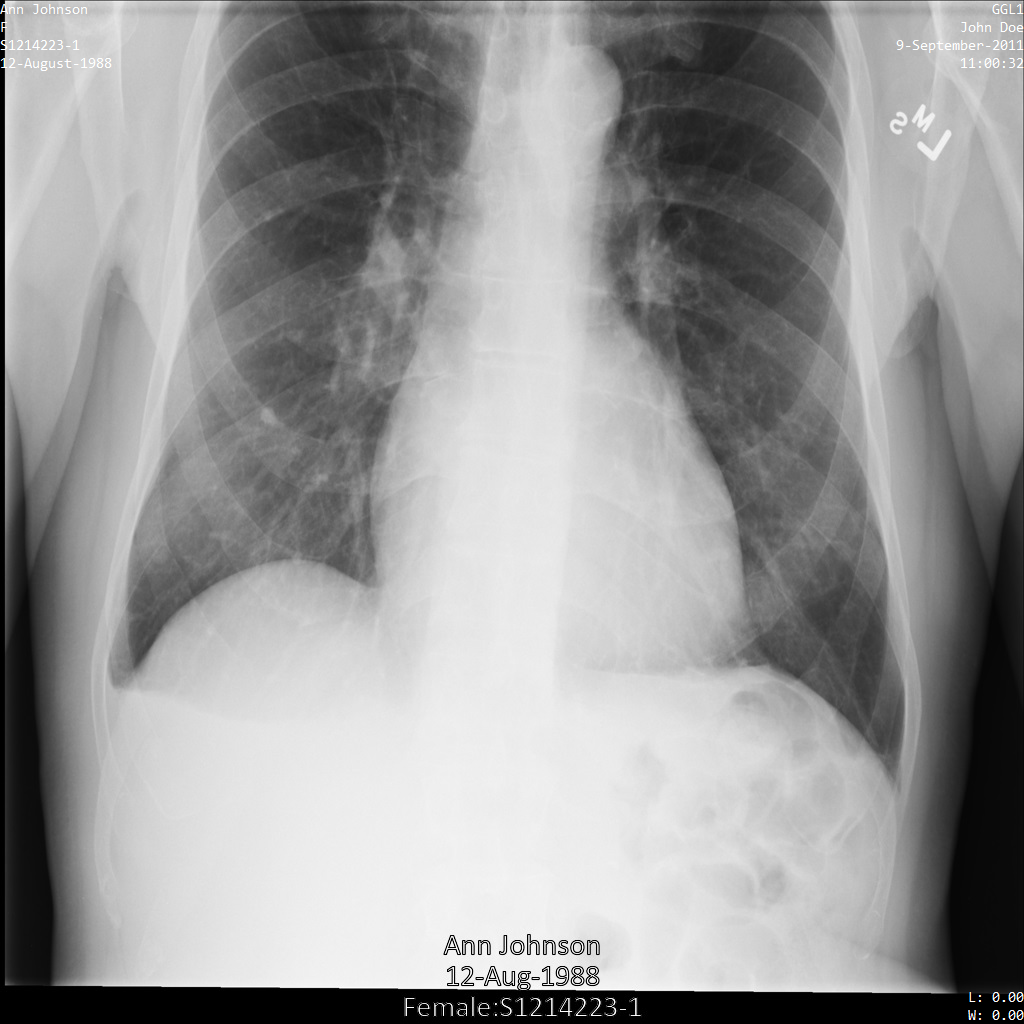

以下各部分提供的示例展示了如何使用各种方法对 DICOM 数据进行去标识化。每个示例都会提供去标识化后的图片输出。每个示例都使用以下原始图片作为其输入:

您可以将每个去标识化操作的输出图片与该原始图片进行比较,以查看该操作的效果。

将图片提交到 Cloud Healthcare API 后,图片显示如下。虽然图片顶部角落显示的元数据已被遮盖,但图片底部的烧屏受保护健康信息 (PHI) 仍然保留。如需一并移除烧屏文字,请参阅遮盖图片中的烧屏文字。